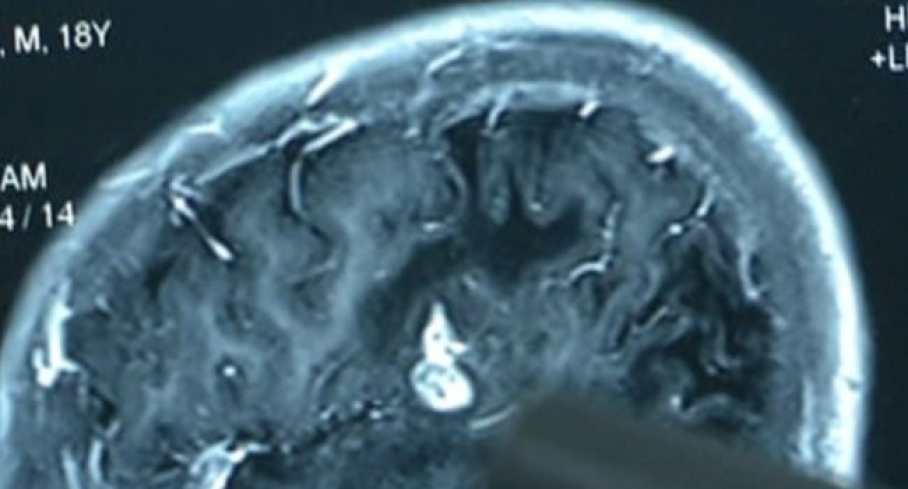

Չինաստանում բժիշկները 23-ամյա տղամարդու ուղեղից մոտ 13 սանտիմետր երկարությամբ կենդանի որդ են հանել: Հաղորդվում է, որ որդը հիվանդի գլխում ապրել է 17 տարի, գրում է The Daily Mail-ը:

Հիվանդն ինքը պատմել է, որ 6 տարեկանից իրեն տարօրինակ խնդիրներ էին անհանգստացնում. վերջույթները քարանում էին: Սակայն ծնողները միշտ անտեսում էին երեխայի բողոքները: Ուստի նա երբեք բժիշկների չէր դիմում` իր վիճակը գենետիկ հիվանդության դրսեւորում համարելով:

Նա դիմել էր մասնագետների միայն այն ժամանակ, երբ վերջնականապես կորցրել էր զգայունությունն իրանի վերին աջ մասում:

Բժիշկները ենթադրում են, որ որդը հիվանդի օրգանիզմում հայտնվել էր հում էկզոտիկ միս, օրինակ` գորտ կամ օձ ուտելու հետեւանքով: